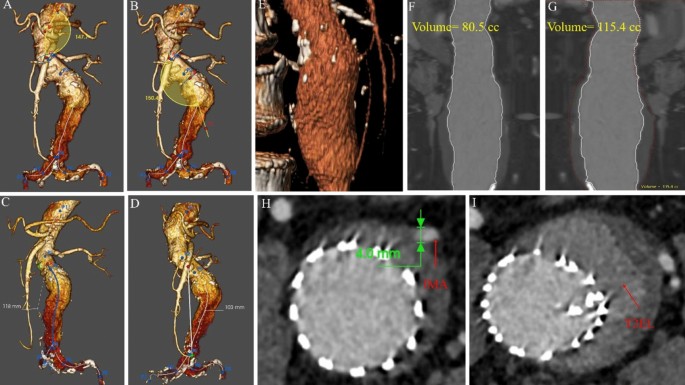

All patients were screened according to the morphology of the aortic aneurysm on CTA. Morphological features were measured using Endosize (Therenva, France) and 3-Mensio vascular (Pie Medical Imaging, Netherlands) software. The measurement methods have been described previously11,12. Definitions of preoperative variables followed the reporting standards of the Society for Vascular Surgery (SVS) and the International Society for Cardiovascular Surgery (ISCS)13,14. The aneurysm features included aneurysm neck features; the neck angle (α), or the angle between the central line of the upper abdominal aorta of the kidney and the central line of the lower AAA of the neck (Fig. 2A); and the neck angle (β), or the angle between the aneurysm neck and the centerline of the aneurysm body (Fig. 2B). The tortuosity index of the aneurysm was defined as the length of the central line of the aneurysm divided by the length of the distance at the beginning and end of the aneurysm (Figs. 2C and 2D).

The morphological features of abdominal aortic aneurysm. (A) Angle (α) is defined as the angle between the central line of the upper abdominal aorta of the kidney and the central line of the lower abdominal aortic aneurysm neck. (B) Angle (β) is the angle between the aneurysm neck and the centerline of the aneurysm body. (C) L1 is defined as the length of the central line of the aneurysm. (D) L2 is defined as the length of the distance at the beginning to the end of the aneurysm. (E) The three-dimensional reconstruction of aneurysm sac by 3-Mensio software for estimating the proportion of thrombus. (F) The volume of blood in the aneurysm sac. (G) The volume of the whole aneurysm sac. (H) The diameter of the inferior mesenteric artery was measured by Endosize. (I) The occurrence of T2EL was identified by CTA.

The aneurysm body volume (ABV) (Fig. 2F), aneurysm thrombus volume (ATV) (Fig. 2G), and the ABV/ATV rate (%VT) were calculated semi-automatically from the lowest renal artery and the aortic bifurcation using the dedicated vessel analysis software 3Mensio Vascular. The arterial diameter was measured using EndoSize software (Fig. 2H), and the occurrence of T2EL was identified by CTA (Fig. 2I).